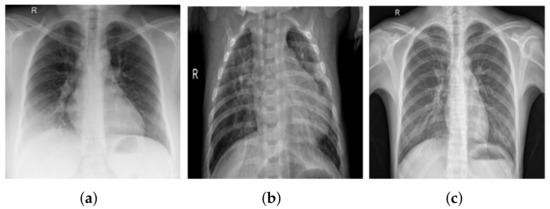

- COVID-19 shows radiological indications that are readily detectable on CXR. As a result, DL-based methods can be used to automatically analyze CXR, significantly reducing the analysis time.

3.1. COV-PEN Image Datasets